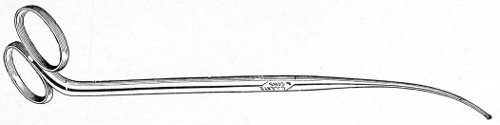

Fig. 4.—Double tenaculum.

The examination of the uterus and other pelvic structures is often facilitated by dragging the uterus downward with a tenaculum while the vaginal or the bimanual examination is being made. Sensation in the cervix is so slight that little or no pain is experienced in this procedure. The anterior or posterior lip of the cervix is caught with the single or the double tenaculum (Fig. 4), guided along the vaginal finger or introduced through the speculum, and the uterus is drawn down by an assistant in case the bimanual examination is being made, or by the external hand of the examiner in case a simple vaginal examination is made. When this is done the utero-sacral ligaments are made tense, and can be felt like two cords extending from the sides of the cervix outward and backward to the pelvic wall. The posterior surface of the uterus can be palpated often as high up as the fundus. The method is especially useful when the examination is made by the rectum, and in this way the whole posterior surface and the fundus of the uterus may be palpated (Fig. 5).

Fig. 5.—Bimanual examination with one finger in the rectum. The uterus is drawn down with the double tenaculum.